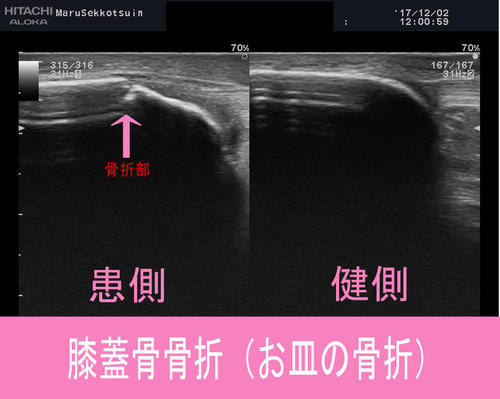

今日の患者さま ゴルフ場で歩行中、凹凸部で足をとられた際、転倒した時に、左膝を捻...